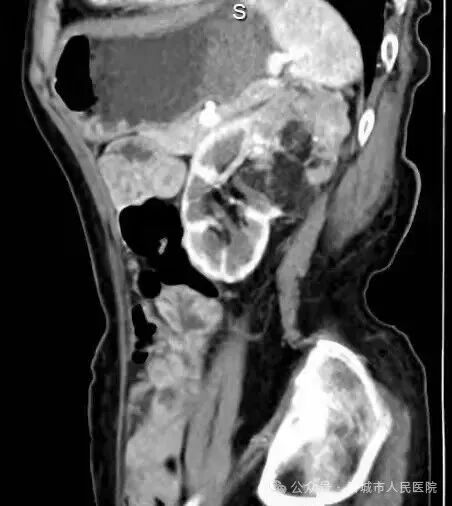

据了解,患者因体检发现左肾占位20余天入院,外院检查提示左肾肿物大小约45*55*98mm,接近十公分的肿瘤体积给治疗带来了极大挑战。更为棘手的是,患者年事已高,体质薄弱且营养状况欠佳,腹壁肌肉薄弱导致手术戳卡固定困难,传统腹腔镜手术操作空间受限、难度极高,而患者及家属保肾意愿十分强烈。

手术过程中,机器人系统的多自由度机械臂展现出独特优势,可灵活模拟人手动作,突破传统腹腔镜的操作角度限制,在狭小的术野内实现精细分离与操作。配合高清3D视野系统,术者能清晰辨识肾脏血管与肿瘤边界,精准把控手术节奏,有效规避血管损伤风险,为肿瘤完整切除和肾脏功能保留奠定了基础。